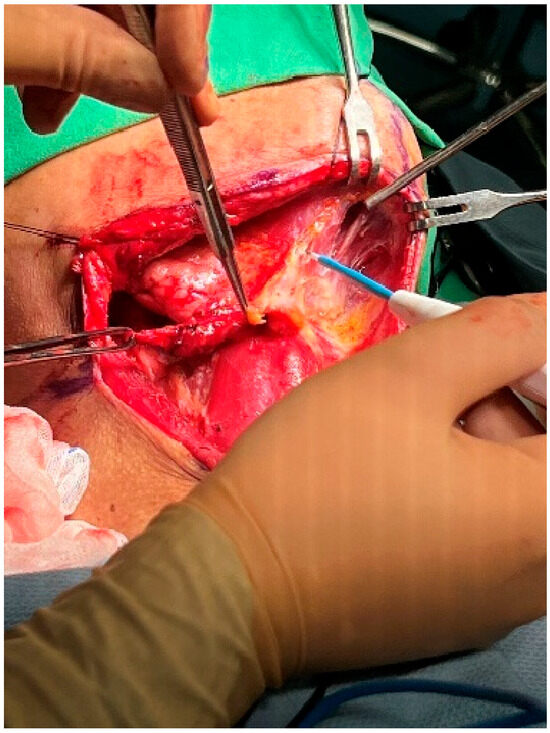

At this point, the neck dissection was complete, and the facial artery was identified, which helped differentiate between the internal and external carotid arteries. By opening the carotid sheath using curved pean forceps, the common carotid artery was made visible. Tracing upward led to the bifurcation of the carotid artery. The presence of branches serves as a characteristic feature of the external carotid artery. The superior thyroid artery, the first branch of the external carotid artery, originates below the level of the greater horn of the hyoid bone. The lingual artery, closely associated with the hyoid bone, originates from the external carotid artery above the level of the greater horn [28]. The root of the facial artery is located obliquely beneath the digastric and stylohyoid muscles [29,30]. These branches were used to identify the external carotid artery. After separating the external carotid artery from the internal carotid artery and vagus nerve, a Rummel tourniquet was used to restrict the external carotid artery and control bleeding (Figure 10).

Figure 10.

Rummel tourniquet restriction of the left ECA.